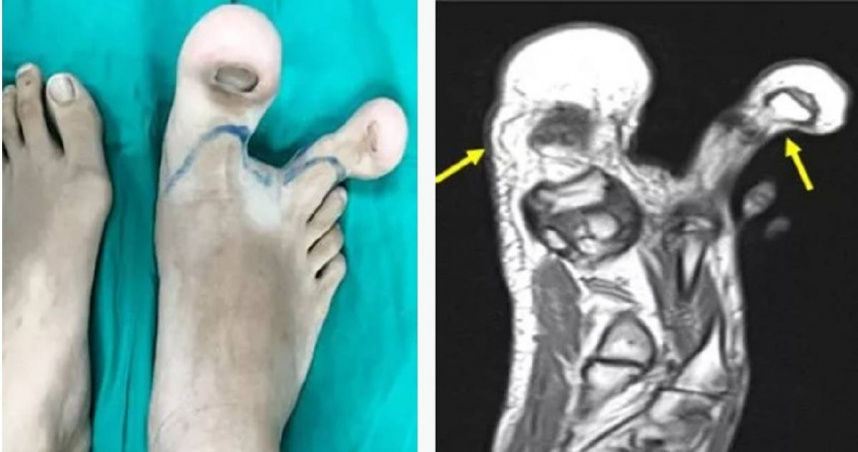

▲少女罹患罕見先天疾病,導致右腳前2腳趾異常腫大。(圖/翻攝自推特)

馬來西亞一名12歲少女罹患俗稱「巨人症」罕見疾病,導致右腳拇指、食指異常腫大如「浩克」,且因症狀會隨著時間不斷惡化,少女與家屬最終在醫師建議下同意截肢。

綜合外媒報導,該名少女因「脂肪瘤性肥大症」(Macrodystrophia Lipomatosa;MDL)惡化到難以行走,被家人送到醫院治療。醫師調閱紀錄發現,少女出生時就被診斷巨人症,但之後未再就醫追蹤,且經核磁共振等多項檢查,確認少女的右腳大拇指、食指蹠骨內側及外側周圍有脂肪組織堆積,並延伸到腳內側足弓。

由於少女右腳腳趾骨骼、肌肉及神經已異常增生,加上症狀會不斷惡化,醫療團隊決定進行「重建手術」,在保留少女足部功能前提下,移除多餘組織。少女手術後恢復情況良好,目前已能穿鞋子行走。